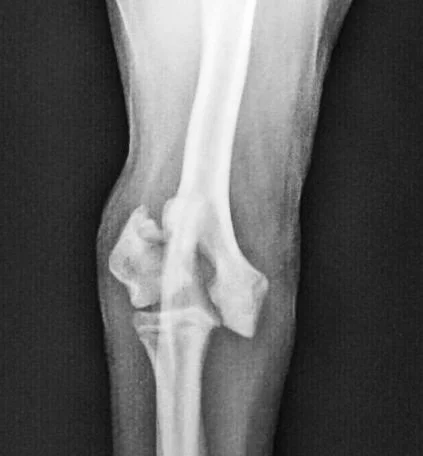

Ununited Anconeal Process

This was a younger, larger, German Shepherd with a condition called elbow dysplasia.  In this disease, portions of the elbow don’t develop properly, and this can be painful.  In this dog, the anconeal process was separated from the rest of the ulna.  We put it back in place, held there with a wire and surgical headless compression screw.  In addition, we performed a dynamic ulna osteotomy (DUO), which helps restore joint congruity as the anconeal process heals.

Before

After